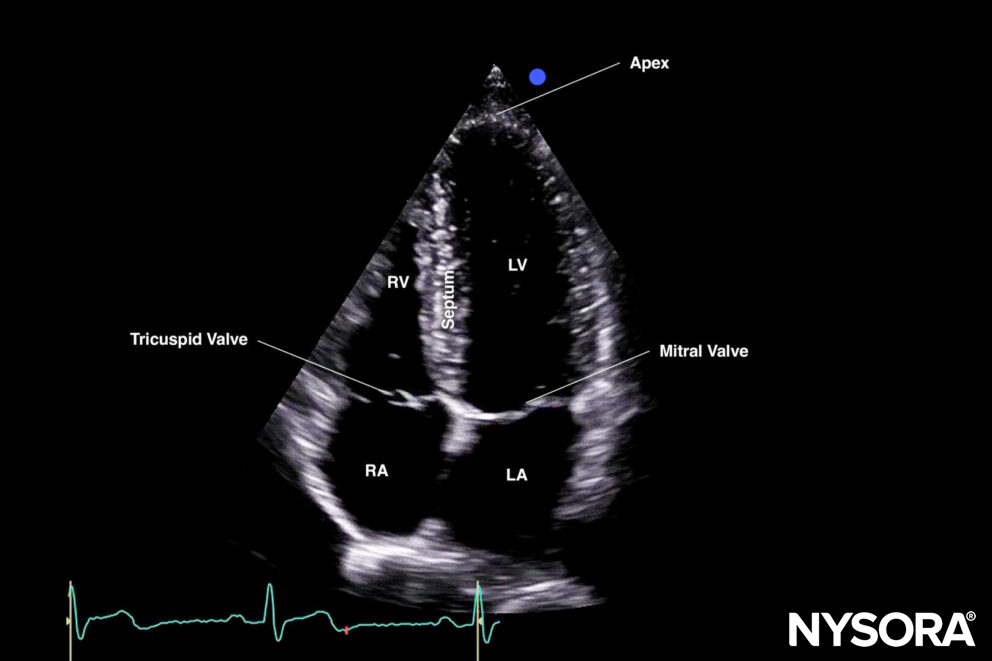

The apical four-chamber view cuts the heart through the coronal plane.

Sonoanatomy of the heart in the apical four-chamber view. Left atrium (LA), left ventricle (LV), right atrium (RA), right ventricle (RV), septum, tricuspid valve, mitral valve, apex.

Reverse ultrasound anatomy:

Reverse Ultrasound Anatomy of the heart in the apical four-chamber view. Left atrium (LA), left ventricle (LV), right atrium (RA), right ventricle (RV), septum, tricuspid valve, mitral valve, apex.

Practical use:

- Left ventricle size and function

- Right ventricle size and function

- Septal kinetics

- Valve function: Doppler